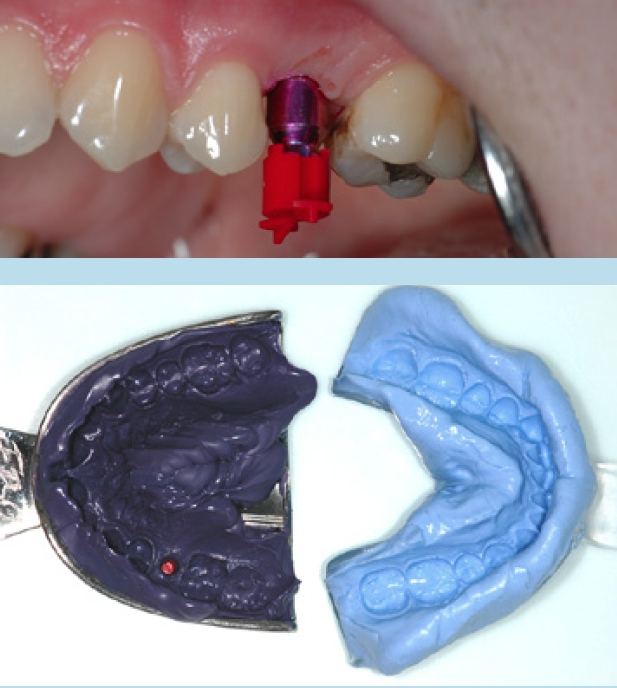

Eine Sonderform der verschraubten Versorgungen stellen Abutments mit abgewinkelten Schraubenkanälen dar. Dabei wird auf Implantatniveau verschraubt, jedoch der Austritt des Schraubenkanals auf einen prothetisch und ästhetisch günstigen Bereich wie die Palatinalflächen der Frontzähne oder die Okklusalfläche der Seitenzähne projiziert. Hierfür ist der Platzbedarf zu berücksichtigen, der für das „Einfädeln“ der Okklusalschraube benötigt wird (Abb. 7).

Abformung

Parallel kann schon mit dem Abutmentdesign begonnen werden. Dabei ist es unerheblich, ob es sich um eine verschraubte oder zementierte Versorgung handelt. Mehrgliedrige verschraubte Arbeiten sollten mit einer Schlüsselprobe geprüft werden, um Spannungen auszuschließen. Die Limitation des Scanverfahrens liegt im Aneinanderfügen vieler Einzelbilder. Das Risiko für Dimensionsabweichungen steigt somit mit der Größe bzw. Weitspannigkeit der geplanten Restauration.

Unabhängig, ob digital oder analog vorgegangen wird, ist bei der Einbringung der Abformpfosten bzw. Scanbodies darauf zu achten, dass diese sich nicht berühren oder die Nachbarzähne touchieren. Liegen Freilegung und Implantation zeitlich weit auseinander und wurde die Lücke nicht provisorisch versorgt, kann es zum Aufwandern der Nachbarzähne kommen (Abb. 14–17). In diesem Fall ist es notwendig, die Abformpfosten zu beschleifen oder das Aufwandern kieferorthopädisch zu behandeln.